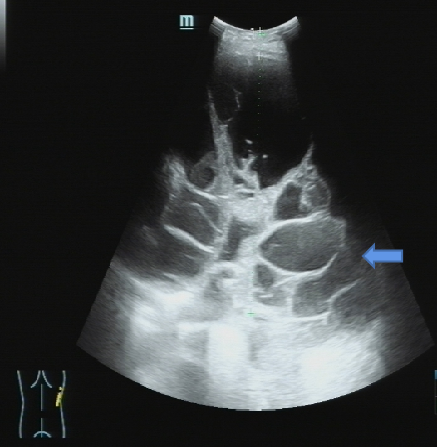

一名71岁男性患者,今年2月因“咳嗽、气促1月余”入住呼吸与危重症医学科,胸部CT显示:(图1)。胸腔积液超声(图2)显示胸水常规提示渗出液。

图2:胸腔积液超声下见单侧胸腔积液伴包裹(蓝色箭头处见包裹)